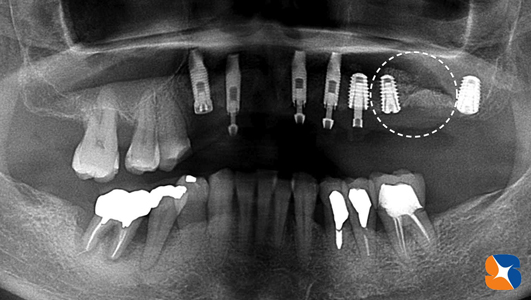

寝屋川市から40代の女性。主訴は「入れ歯で苦労している。医療従事者でしゃべる仕事をしている。上顎の骨が薄くて浅いのでインプラントは難しいと言われ続けてきた。先生の御意見をお聞かせ下さい。」

CTを使って骨の状態(骨の厚みと高さ)をチェックすると、厚みも高さもかなり不足していましたので、インプラント治療をするのなら人工的に骨を増強する必要がありました。また、黄色の点線の歯は、乳歯のようにグラグラしているので、抜歯をして当日その痕にインプラントを移植することもお伝えしました。

この画像は、ほお骨の横から人工骨を入れた所に、インプラントを植立したところです。

•抜歯2本→抜歯痕にインプラントを2本移植

•2㍉幅のほお骨の横から穴を開けて人工骨を増強する手術(サイナンスリフト)

•7連結の仮歯をセットして帰っていただく。